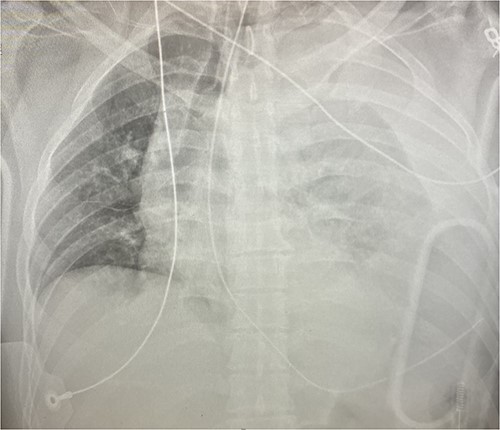

Given his hemodynamic normalization without ongoing transfusion requirements, he was taken to the computed tomography (CT) scanner for axial imaging of the head, chest, abdomen and pelvis. A CT angiogram of the chest revealed trace pneumopericardium and pneumomediastinum with trace hemopericardium. A 1.7 × 0.7 cm out-pouching at the anterior aspect of the right ventricular apex concerning for a traumatic pseudoaneurysm was also detected (see Figs 2 and 3). His other injuries were notable for subarachnoid and subdural hemorrhages, left temporal bone fracture, open mandibular fracture, left 3–6th, 10th and 11th rib fractures, a 4th lumbar vertebrae burst fracture with 1st and 3rd lumbar vertebrae compression fractures, 8–11th thoracic vertebrae compression fractures, and a left femoral neck fracture. He was subsequently transferred back to the trauma bay where a formal trans-thoracic echocardiogram was immediately performed, which demonstrated a dyskinetic area of the right ventricular apex with paradoxical out-pouching during systole—suggestive of pseudoaneurysm and confirming the diagnosis on axial imaging.

Axial CT imaging demonstrating pseudoaneurysm of right ventricular free wall rupture.